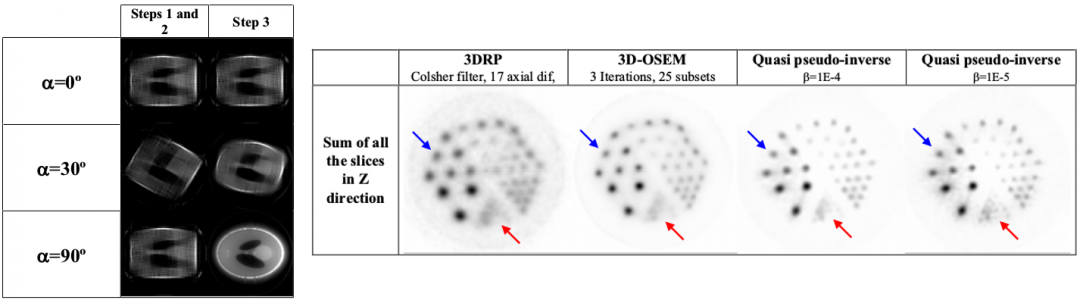

A new reconstruction strategy is proposed for 3D images acquired with rotating PET scanners. This method is based on the decomposition of the system response matrix (SRM) into a projection and a rotation components that are inverted independently. We present the rationale of the new reconstruction procedure as well as some examples to compare with analytical 3D reconstruction (3DRP) and 3D statistical reconstruction (3D-OSEM).